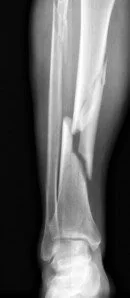

• Tibia and Fibula fracture-- broken legs and ankles can leave a person with poor mobility or even one leg shorter than the other. Active persons who participate in sports may be unable to do so after a tibia or fibula fracture.

• Compound fracture-- compound or open fractures break the skin around the broken bone. These types of fractures often result in infection because the injury is open to the outside world. If an infection occurs, bone healing can be complicated. Compound fractures usually require surgery.